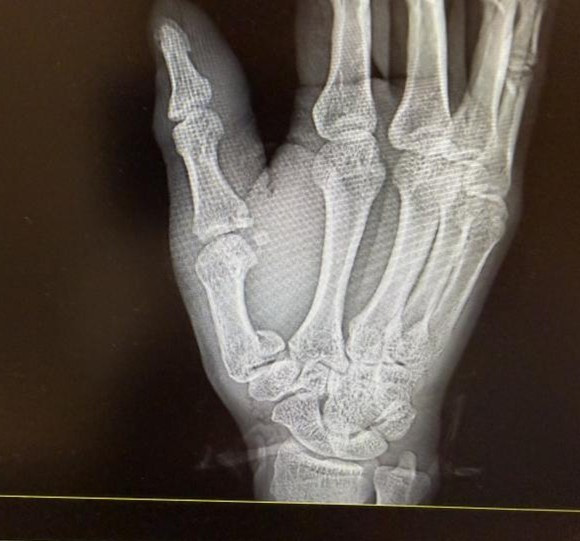

一问才知谈,李先生带着女儿在郊区放冲天炮,没承思操作时出了偶而,手被冲天炮炸伤了。值班医师刘建勇初步查验后,怀疑不仅是外伤,还可能归拢骨折,飞速为他作念了消毒包扎止血,安排拍片还打了破感冒针。

拍片成果印证了刘建勇的判断,李先生右手第一掌骨、第一近节指骨基底部齐骨折了。刘建勇为他的伤口作念了清创缝合,随后骨科医师也实时介入,作念了临时石膏固定,后续李先生还得入院择期手术。

病院供图